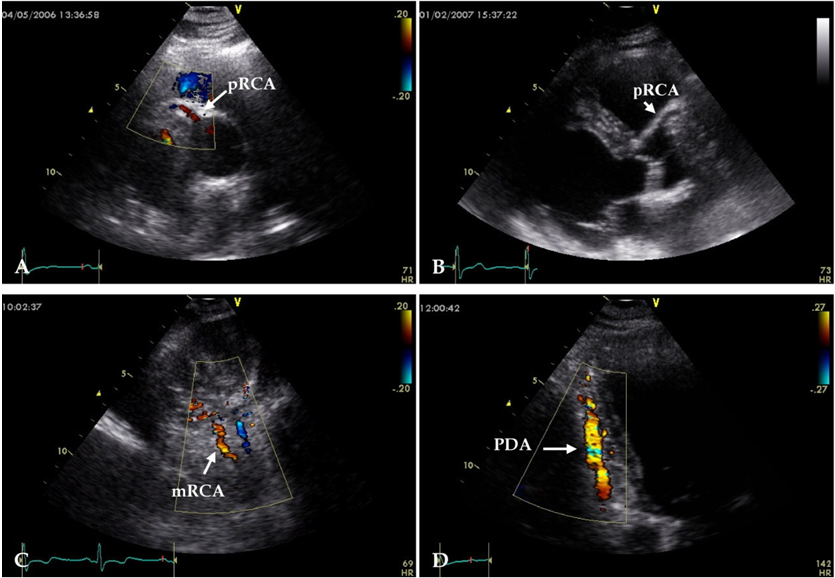

左冠状动脉起源异常的超声特征和外科治疗结局

图片尺寸535x365